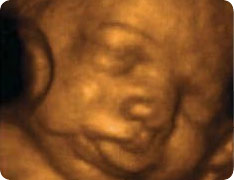

Плод сосет палец — УЗИ плода 4d